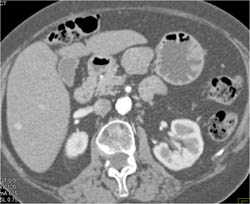

Diagnosis

GIST Tumor